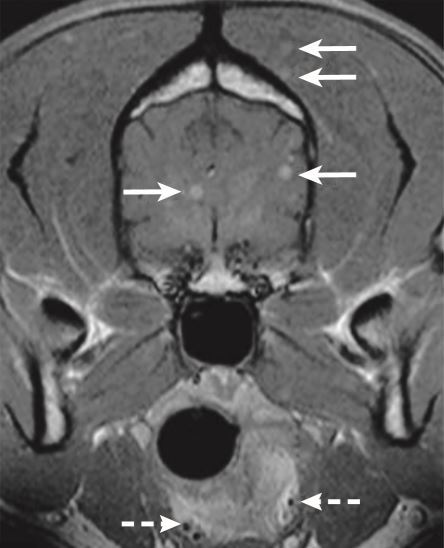

What artifact is this?

A

CSF flow artifact causing a pseudolesion

22

Q

What direction is the pulsatility artifact seen in?

Phase encoding and only in this direction